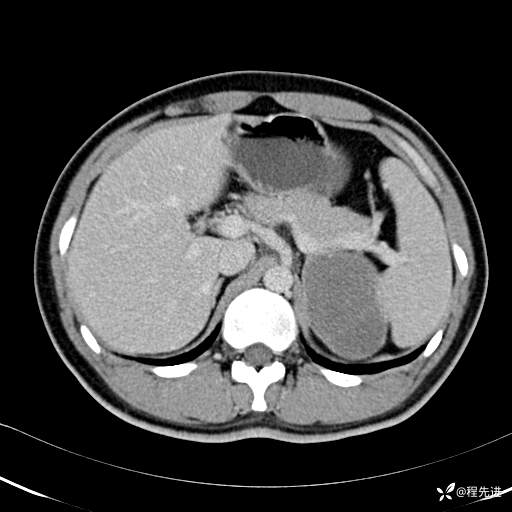

【腹盆】特别精彩病例|体检发现的左侧腹膜后占位期待您的精彩解读

患者年龄:25岁

简要病史:体检发现

CT平扫:(CT值:平扫,27HU,动脉期,27HU,门静脉期,31HU,平衡期,32HU)

门静脉期: